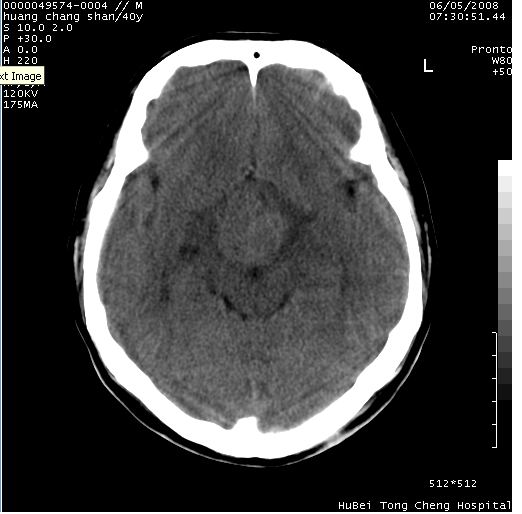

患者 m,40y。头痛,视力模糊,多饮多尿,性欲减退半年余。

行ct平扫+增强,图象如下:

鞍上占位性病变,考虑:

1、脑膜瘤

2、垂体瘤

3、建议mr检查

结合临床考虑鞍上生殖细胞瘤可能性大于脑膜瘤(增强未见脑膜围征),建议结合冠状位扫描看病灶起源及垂体窝、鞍底情况。垂体窝内未见明显软组织密度影,垂体窝未见扩大,暂不考虑垂体瘤;病灶较大,未见囊变及钙化,颅咽管瘤不支持。期待结果!

2、ct表现:肿瘤呈类圆形,均匀略高密度,无囊变,无钙化。侧脑室有扩大。